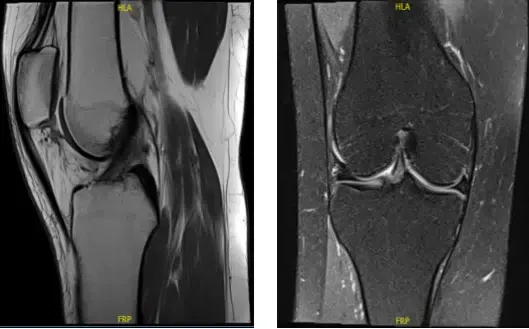

Se revisó y discutió la resonancia magnética; Para el dolor de rodilla derecha no se identifica fractura, luxación, proceso de reemplazo de médula ni lesión osteocondral.

El tendón distal del cuádriceps, la rótula y el ligamento rotuliano aparecen dentro de límites normales. Se identifica una lesión ovalada lobular de 0,6 x 0,9 x 1,7 cm, que presenta baja señal en TI y señal heterogénea en T2, entre la faceta rotuliana lateral y el fémur anterior en la región de la articulación patelofemoral y puede representar cambios fibróticos.

El ligamento cruzado anterior, el ligamento cruzado posterior, el ligamento colateral medial y el ligamento colateral lateral están intactos. No se identifica masa de tejido blando ni señal anormal en la musculatura. Se identifica una ruptura oblicua en el cuerno posterior del menisco medial. El menisco lateral está intacto y no se ha identificado ningún desgarro.

Con impresión de desgarro oblicuo en el cuerno posterior del menisco medial. Se identifica una lesión ovalada lobular de 0,6 x 0,9 x 1,7 cm, que presenta baja señal en TI y señal heterogénea en T2, entre la faceta rotuliana lateral y el fémur anterior en la región de la articulación patelofemoral y puede representar cambios fibróticos.

Resonancia magnética de rodilla derecha sin contraste